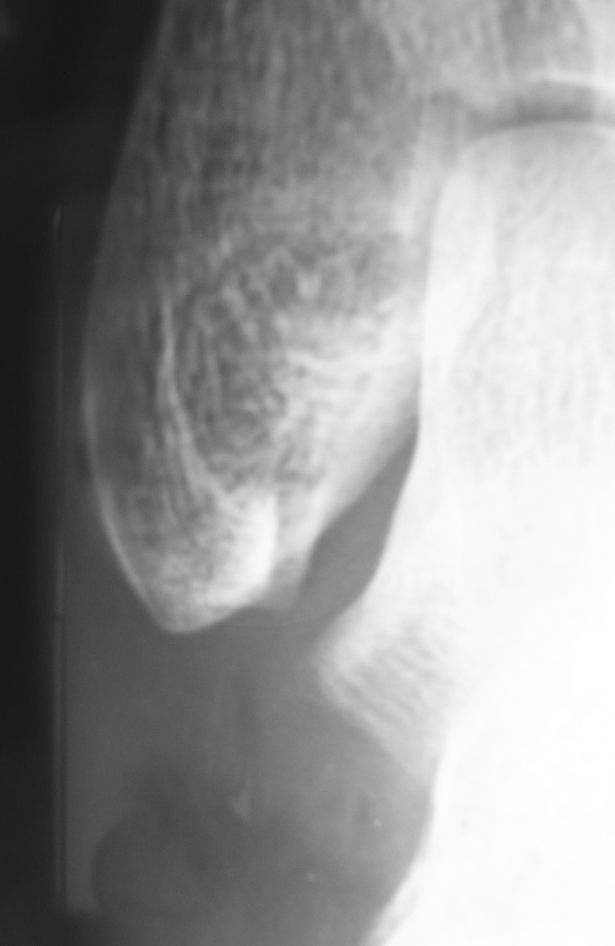

転位が小さいのでU字スプリントで保存治療を行っています。念のために受傷後1週に単純X線像を撮影して転位が増大していないことを確認しました。その際の画像は下記のごとくです。

初診時と微妙にX線の入射角度が異なるため、腓骨遠位端の骨折が全く分からなくなっています。もし順序が逆なら「骨折は無さそうです」と説明してしまうところでした。